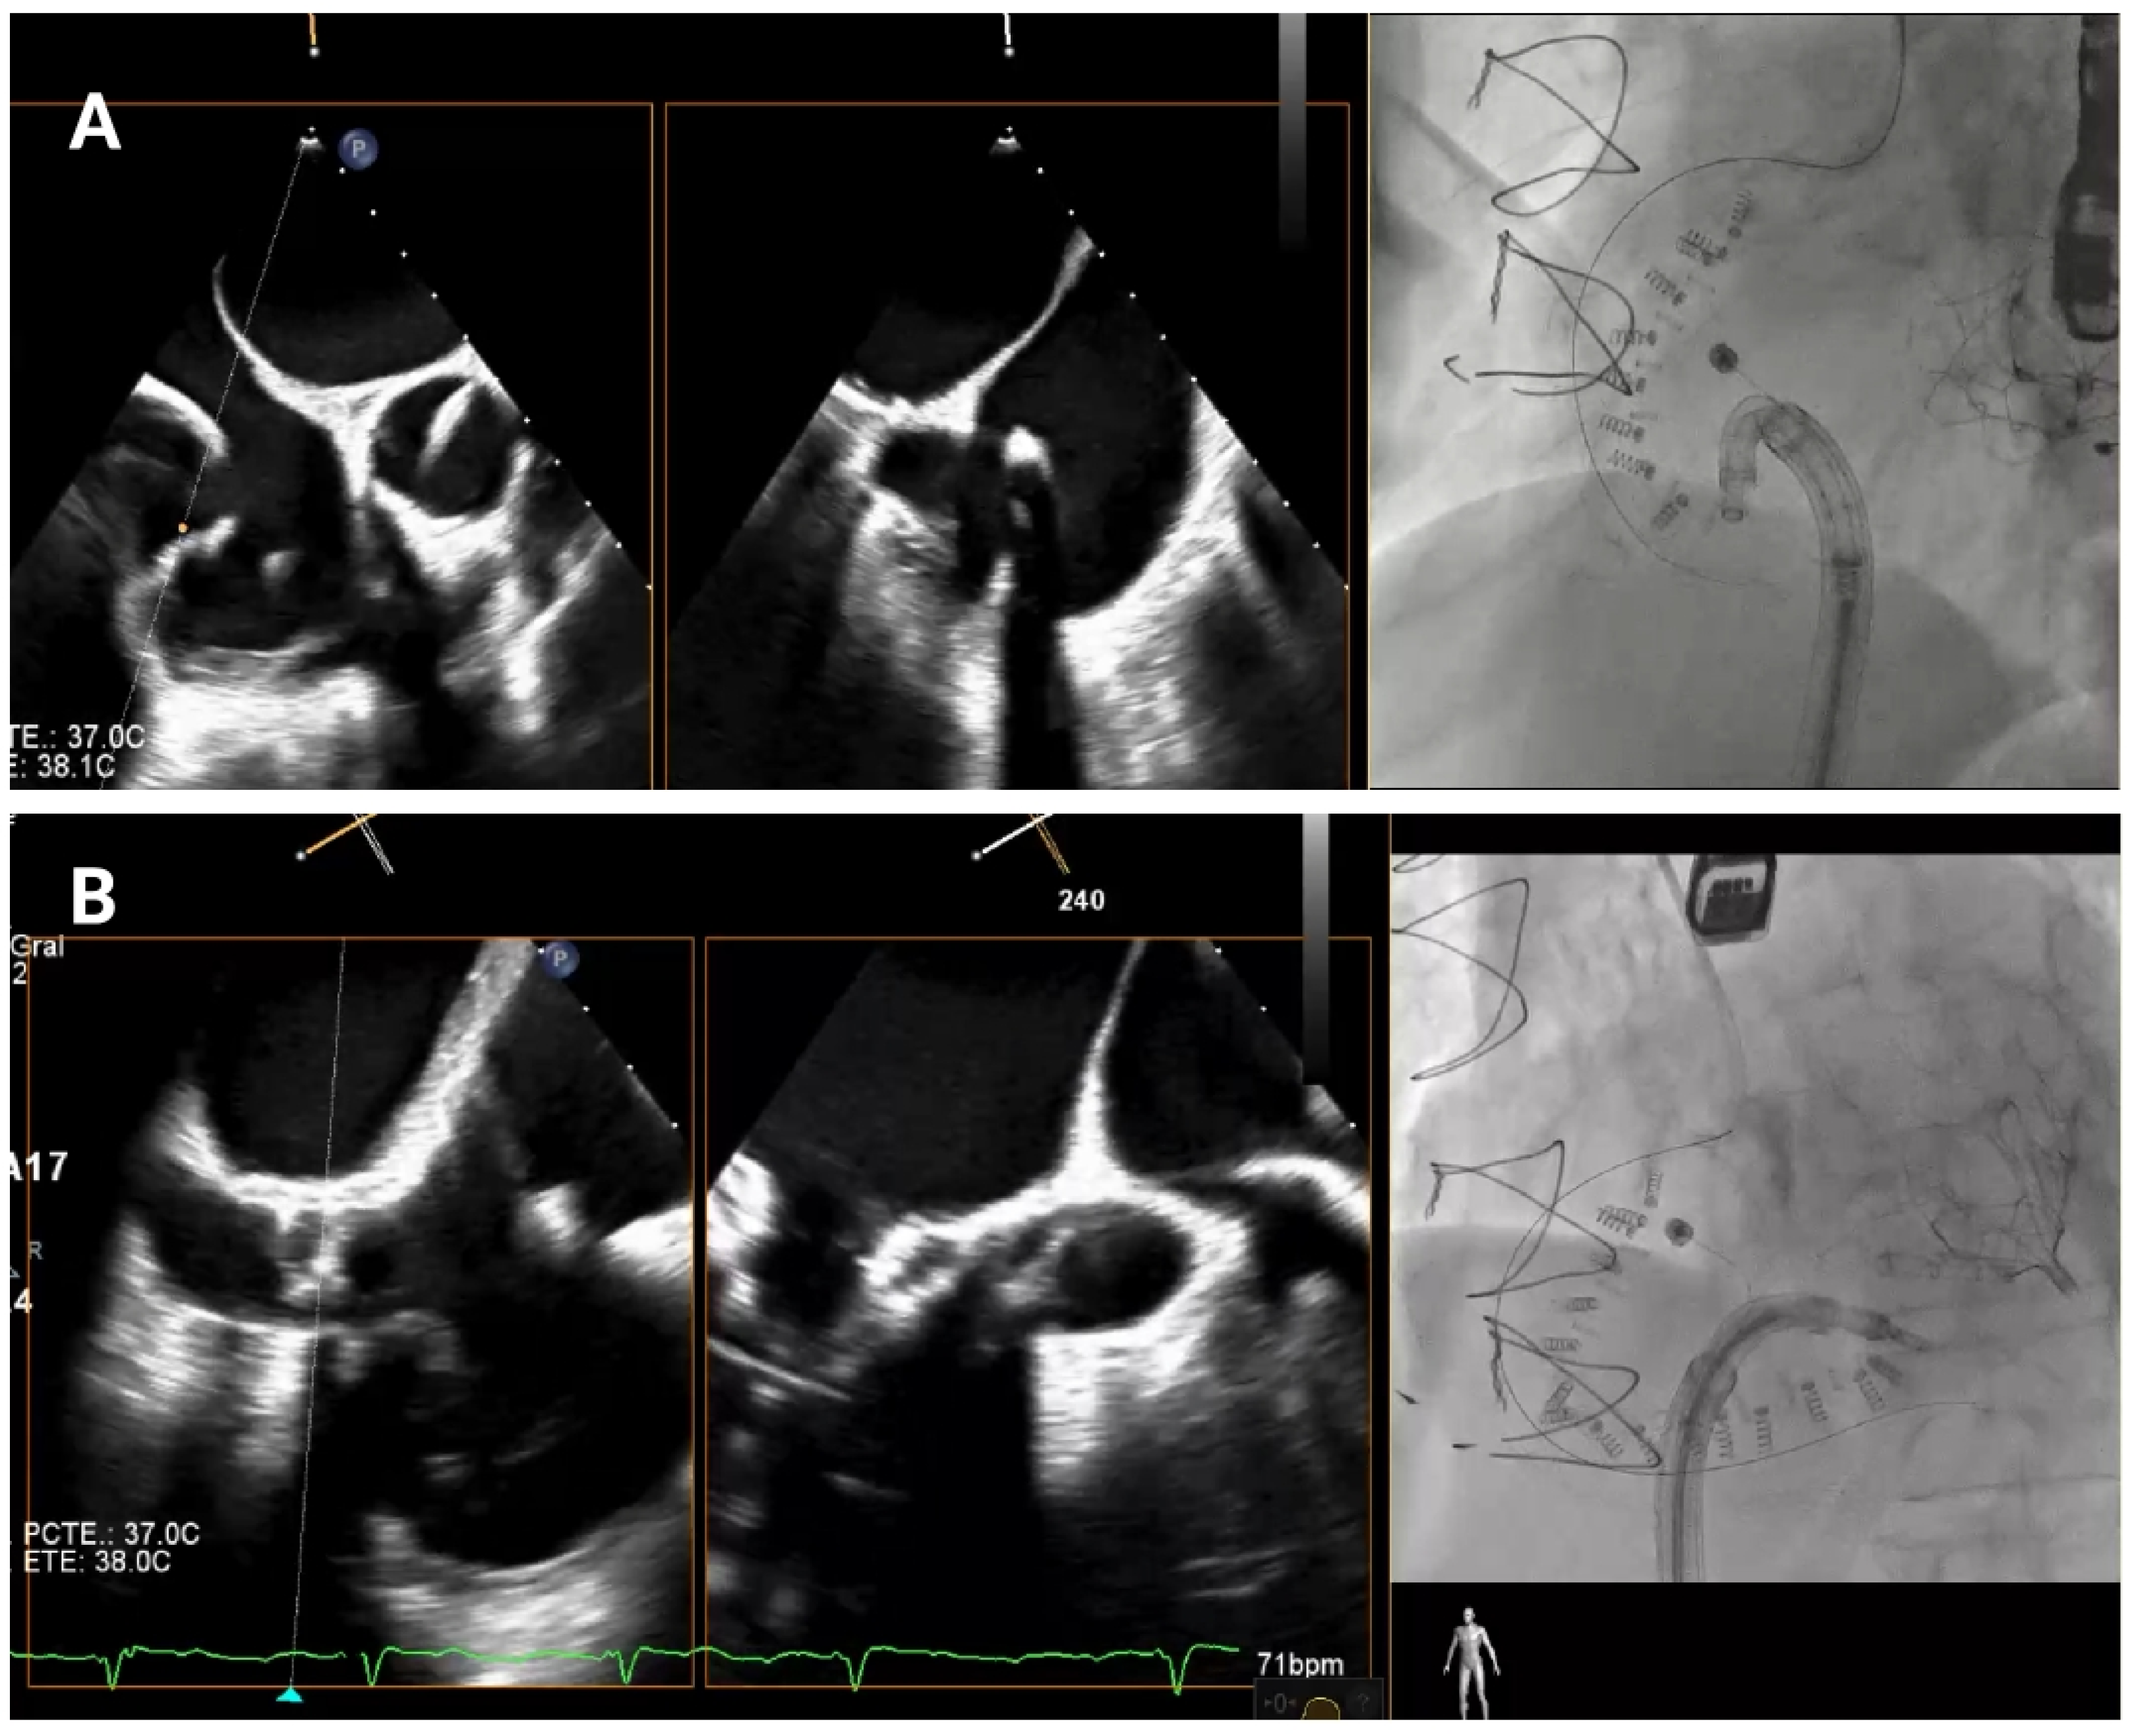

4.4. Band Cinching

In the final release phase of the procedure, the size adjustment tool (SAT) is advanced to contract the Cardioband implant (

Figure 7), a crucial step in securing the device around the tricuspid annulus and effectively reducing the diameter. This reduction is performed in incremental stepwise adjustments, which range between 0 cm and 2.5–3.5–4.5–5.5 cm depending on the chosen band size, to achieve optimal tension and alignment with the annulus. Continuous real-time monitoring with TEE and fluoroscopic imaging is essential during this phase to confirm successful positioning and ensure gradual tightening without impinging on surrounding structures or compromising valve function.

Figure 7.

Band cinching and post-implant assessment. The size adjustment tool is used to cinch the Cardioband, reducing the tricuspid annular diameter by 3.5–5.5 cm depending on the band size. Pre-cinching (A) and final result post-cinching (B).